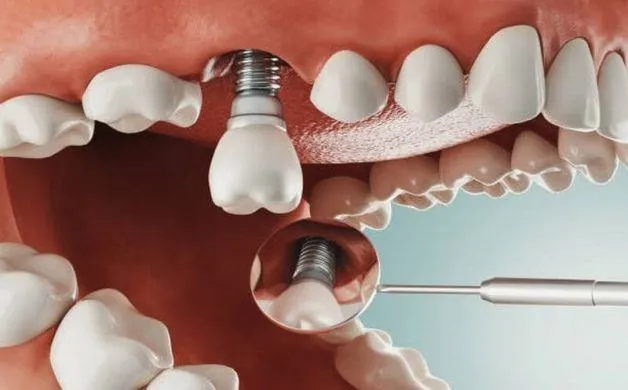

Công nghệ trồng răng implant được áp dụng lần đầu tiên 1952 bởi Branemark (Thụy Điển). Từ đó đến nay, công nghệ trồng răng implant luôn luôn

Cấy ghép Implant là kỹ thuật nha khoa phức tạp. Kỹ thuật này đòi hỏi bác sĩ phải có trình độ chuyên môn giỏi, tay nghề cùng

Cấy ghép implant là phương pháp hiện đại để khôi phục răng cho những người mất răng. Công đoạn này bao gôm từ việc phục hình từ